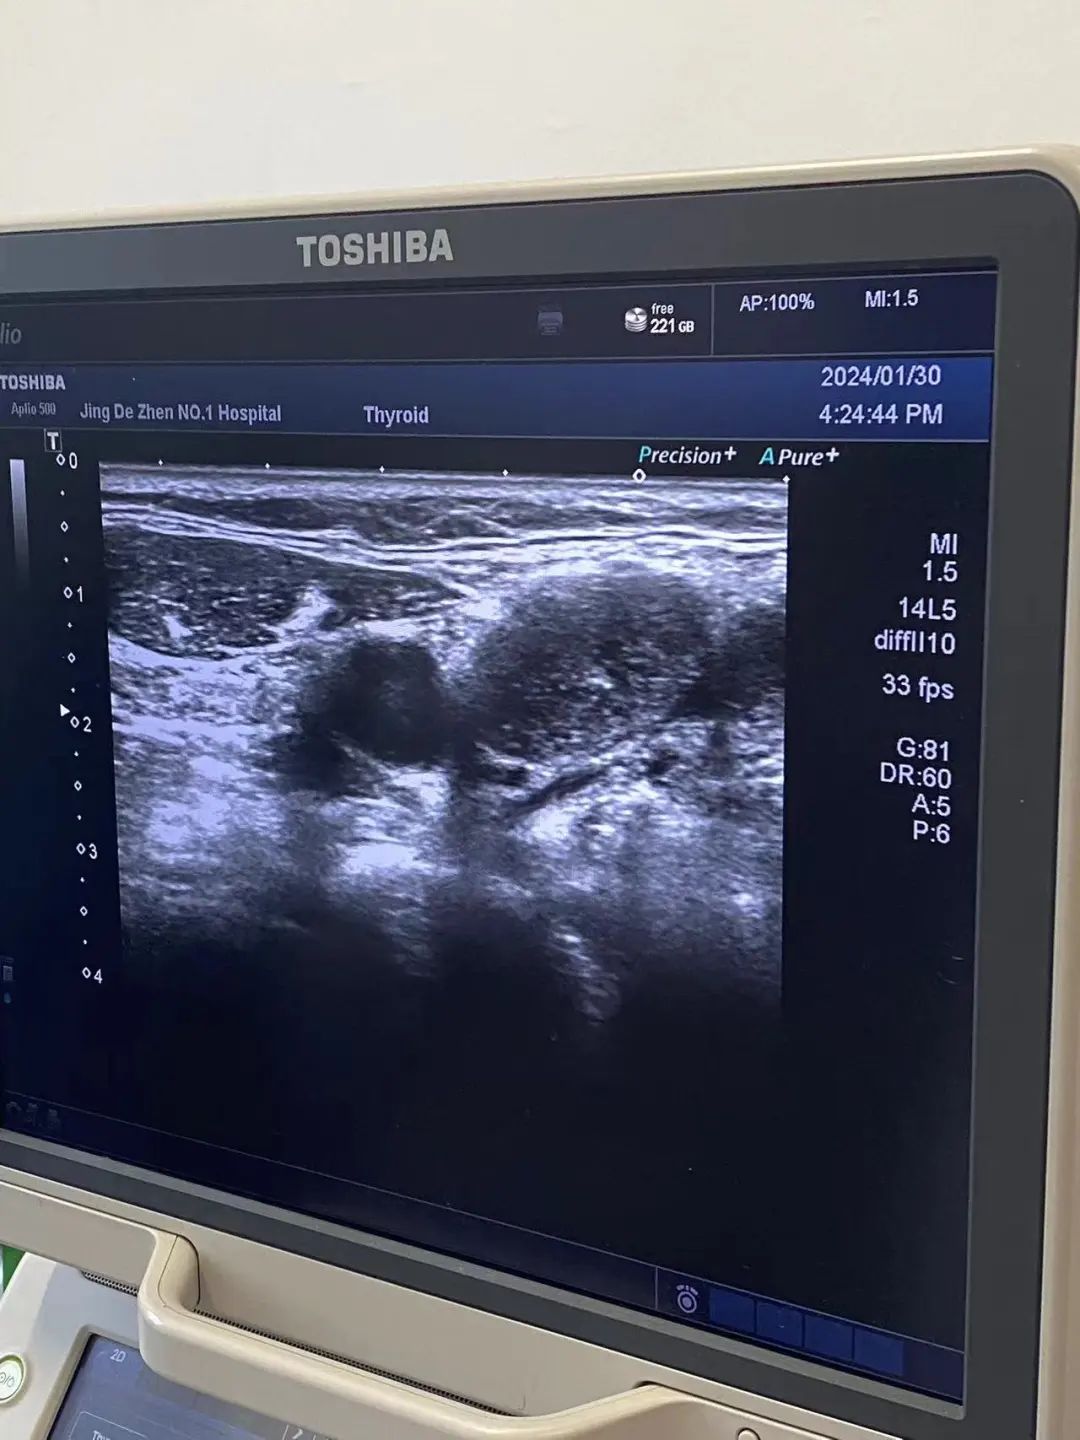

颈部肿物穿刺活检术一般是指在B超定位下进行穿刺,对可疑的肿物、结节,通过精准穿刺取出一部分组织,送病理科明确病因。穿刺的过程先在B超定位下找到包块,选中穿刺部位,进行消毒、铺巾,将穿刺针沿定位方向进行穿刺,得到组织。耳鼻咽喉头颈外科仇晓露表示,该操作导致的疼痛及出血的风险都比较小,可以明确颈部肿物的性质,临床运用广泛。对于王某,B超定位下的穿刺是最简洁、安全、高效的检查方式,同时也为后续治疗明确了方向。

70多岁的高龄患者王某,因右侧下颌发现肿物8年多,现已皮肤溃烂,于是来到景德镇市第一人民医院耳鼻咽喉头颈外科进行治疗。因颈部肿物的性质不明确,无法确定进一步治疗方案,经家属同意后,该科主任方小明、副主任仇晓露为患者进行了B超引导下颈部肿物穿刺活检术,在颈部超声全面探查下确定了穿刺点和穿刺路径,局麻完成后,用活检针精准刺入,顺利取得肿物组织,手术伤口小,患者没有任何不适感。通过组织活检,为舌下腺及下颌下腺恶性肿瘤。于是,手术团队后续为患者成功切除舌下腺及下颌下腺恶性肿瘤,目前患者已恢复并出院。